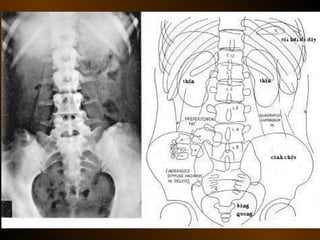

TỤ DỊCH NGOÀI PHÚC MẠC

• Khoang quanh thận

– thận, tuyến thượng thận, niệu quản

• Khoang cận thận trước

– tá tràng, tụy, đại tràng lên, đt xuống

– động mạch gan, lách

• Khoang cận thận sau

– Động mạch chủ bụng, bạch mạch

– Thân đốt sống

– Tá tràng, tụy, đường mật, đại tràng

– Ruột thừa sau manh tràng, đm gan, lách